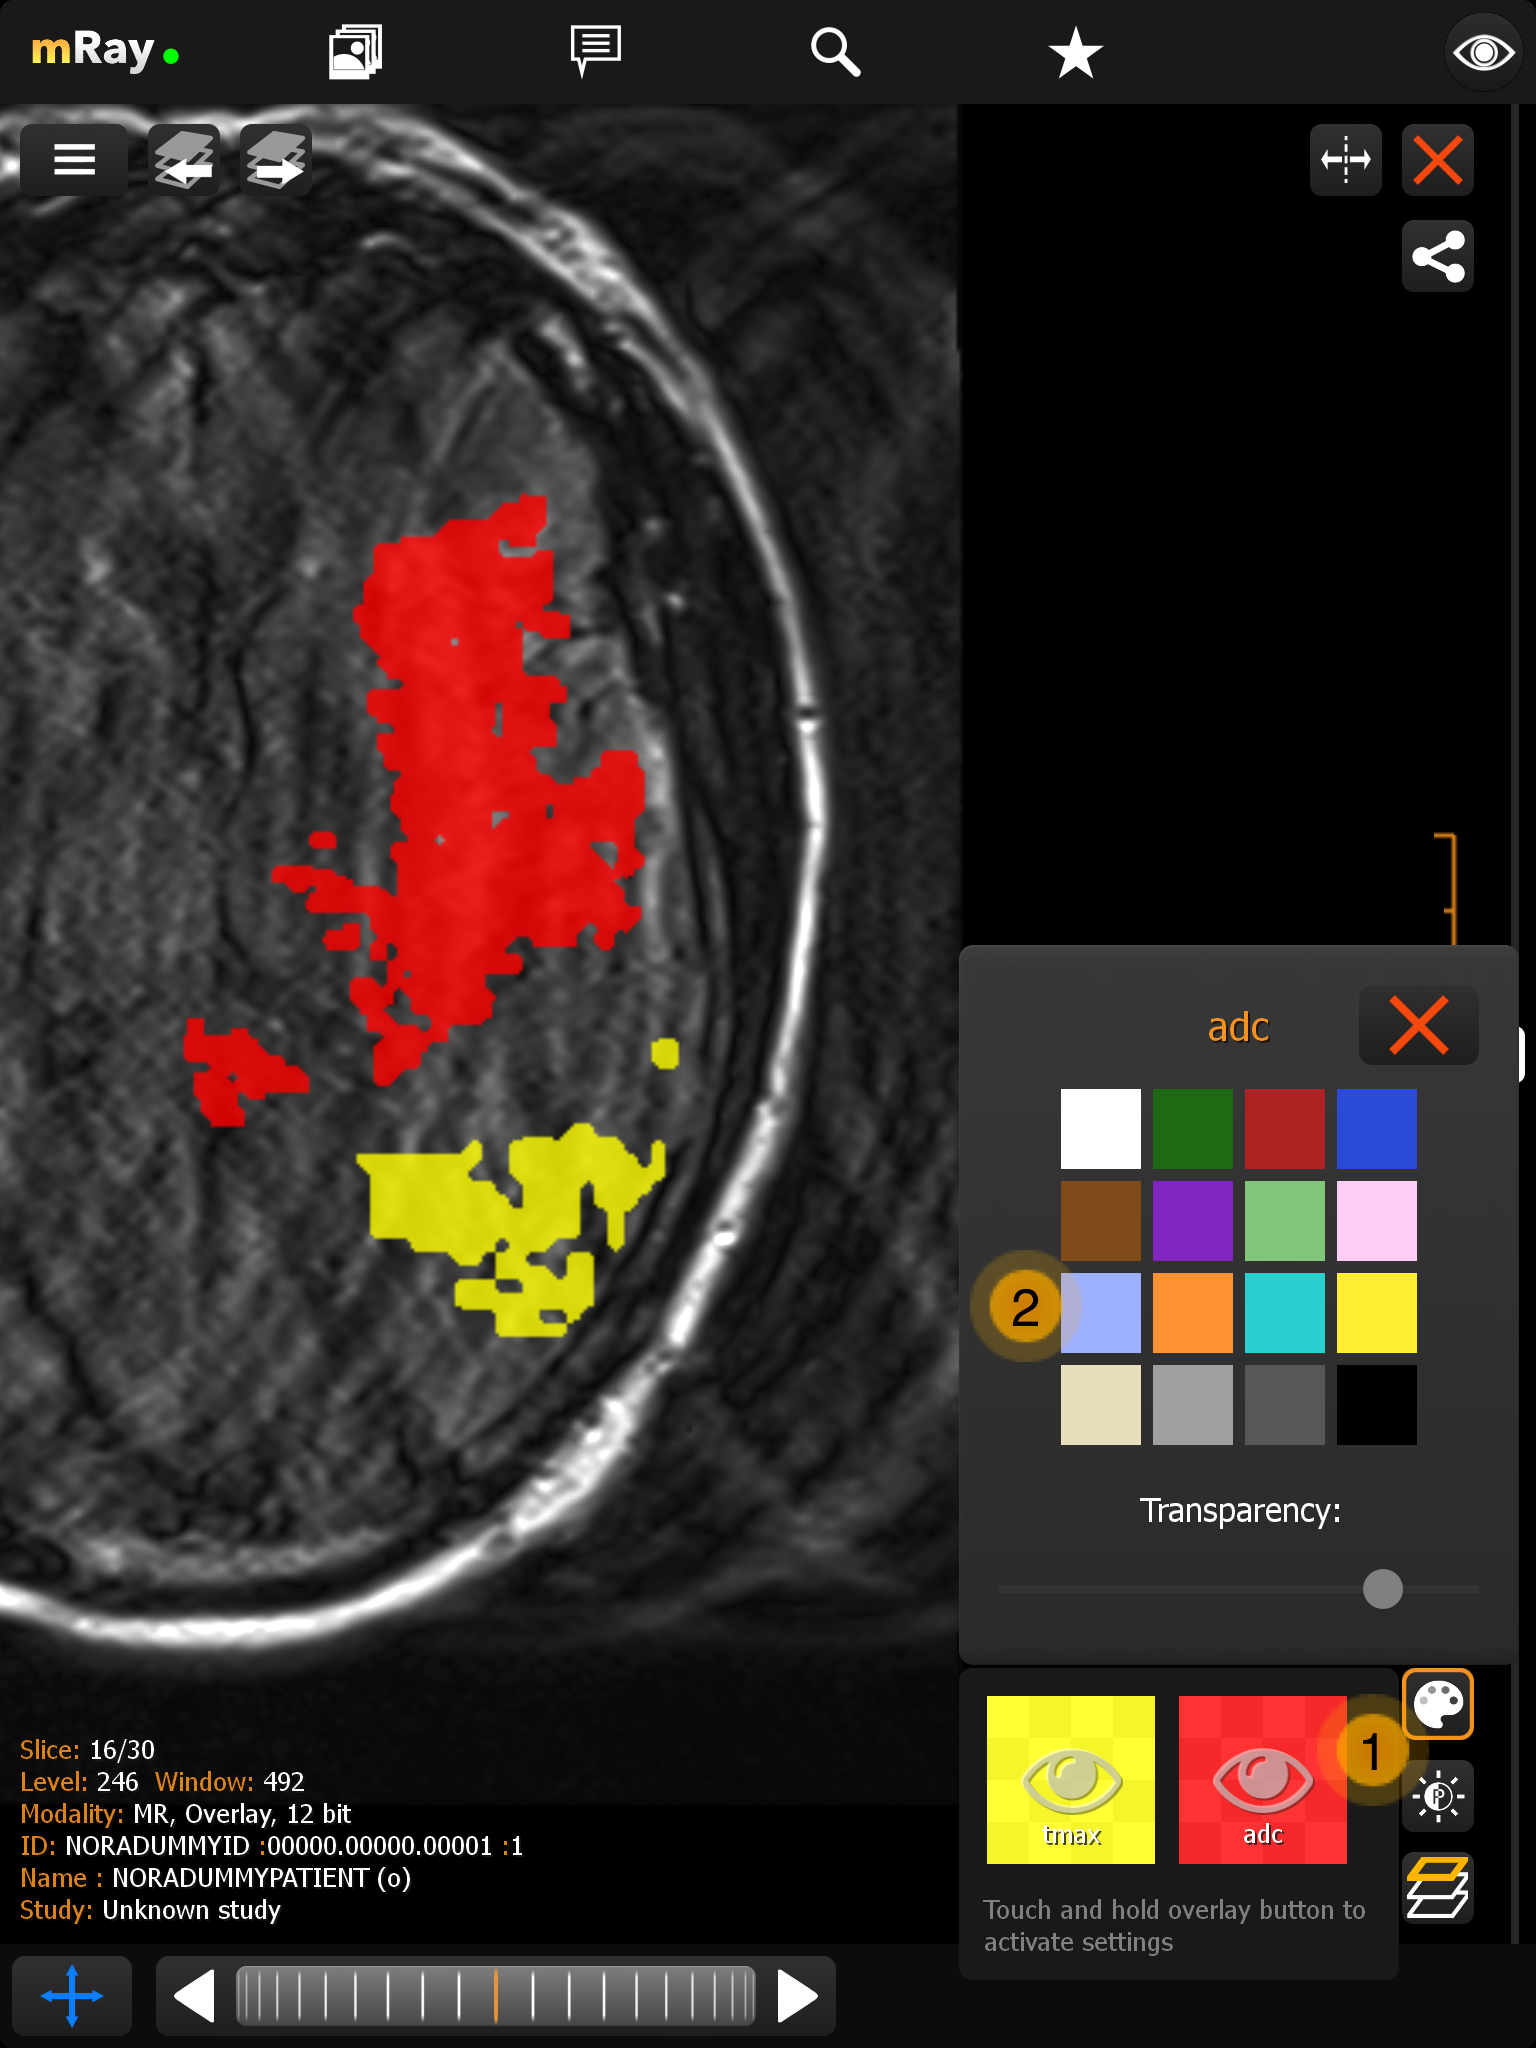

11.2. Overlay Menü

mRay unterstützt die Anzeige von DICOM Dateien mit bis zu 16 Overlay Masken. Diese Overlays können über ein Menü im Viewer getrennt ein- bwz. ausgeschaltet werden. Außerdem ist es möglich jedem Overlay eine freiwählbare Farbe und Transparenz zu vergeben.

-

Zeigt das Overlay mit Farbe und Label information. Mit einem Klick können Sie das jeweilige Overlay an- bzw. ausschalten. Um die Farbe und die Transparenz anzupassen, halten Sie den Button für kurze Zeit gedrückt.

-

Hier können Sie die Farbe und die Transparenz für das Overlay einstellen